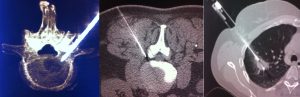

- Guida molto precisa nelle biopsiea carico di un organo interno o come guida a punture-infiltrazioni mirate in organi e siti delicati (infiltrazioni di farmaci ed ozono-terapia intradiscale e foraminale colonna vertebrale ed articolazioni;

- Guida nell’esecuzione di interventi minimamente invasivi e delicati (radiologia interventistica TC guidata agobiopsie)

Le ricostruzioni 3D, VR e MIP sono particolarmente utili non solo nel rappresentare lo scheletro e quindi le fratture complesse ma anche nello studio accurato delle strutture vascolari e degli organi profondi. Un particolare software permette di ottenere delle dettagliate immagini di tipo endoscopiche trova impiego nella colonscopia virtuale e anche nella broncoscopia virtuale, esami particolarmente utili soprattutto quando l’esame endoscopico non puo essere eseguito o quando viene interrotto. Altra fondamentale applicazione è la TC ad alta risoluzione del polmone, un esame che viene acquisito o successivamente ricostruito con precisi parametri dedicati per lo studio delle più fini strutture polmonari utile nello studio delle patologie interstiziali polmonare (HRTC).